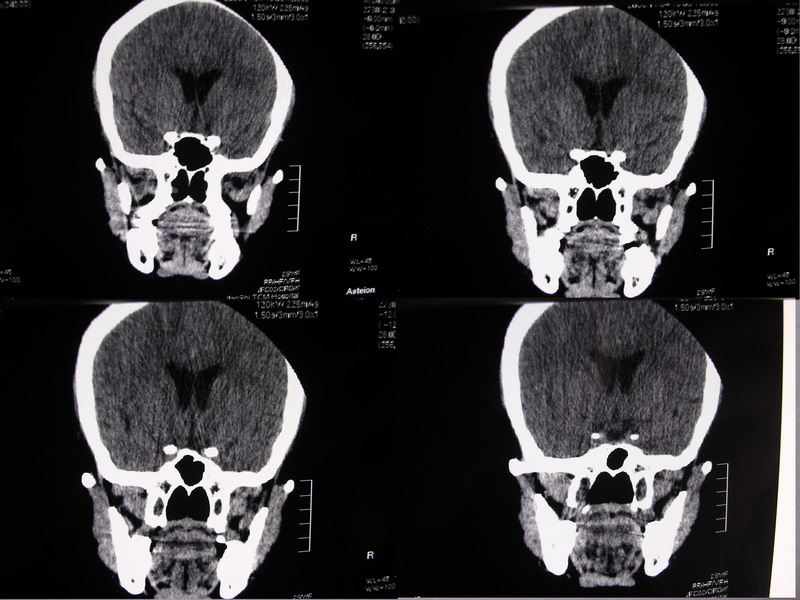

向××,女,29岁,二十天前高热,抗炎治疗后双眼斜视,肌无力,双下肢张力ii级。

奇怪啊!临床症状那么典型,为什么没有什么脑炎的迹象?二十天了,应该有表现的,是我眼拙?但小脑蚓部以及左侧颅中窝均属正常我应该没有看错,大汗淋漓!渴望老师们指点迷津!

除侧脑室额角轻度扩大外,余未见异常。

侧脑室稍扩大,余未见确切异常强化征,请结合脑脊液及脑脊髓mri检查

侧脑室稍扩大,余未见明显异常强化征。

双侧脑室有轻度扩大,增强看脑沟裂显示还是模糊的.时间较长应该考虑脑膜炎.